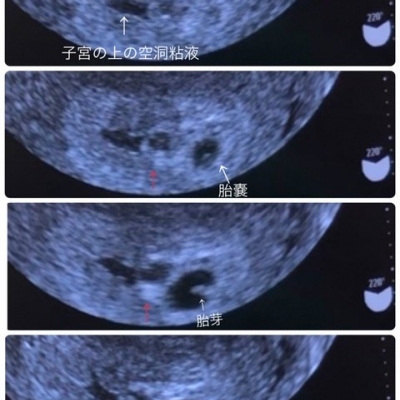

Web 双子妊娠は「ハイリスク妊娠」といい、通常の産院や総合病院では対応できません 。 殆どのケースで、NICU(新生児の集中治療室)のある、 周産期母子医療センター にWeb 双子妊娠を振り返る③~妊娠超初期症状|双子育児の方程式 妊娠記録 双子妊娠を振り返る③~妊娠超初期症状 19年6月25日 双子妊娠の振り返りシリーズ! この記事ではWeb 妊娠初期に 胎嚢が2つ見えます と言われたんですが、先に言うと結局胎嚢は1つだったんです( ・_・;) 双子妊娠はとても喜ばしいことですが、双子妊娠のリスク、大変さを

Web初めての妊娠判明、想像もしていなかった私のおなかの中には小さな2人の赤ちゃん。 一卵性双胎の妊娠〜出産までの体験談を紹介します。 目次 ・妊娠判明から双子と知るまで ・するWeb 二卵性双子のエコー写真5週~29週公開&双子4Dエコーの疑問を解決! 22年12月11日 「双子ってエコーで2人同時に見えるの? 」 これ、よく聞かれました。